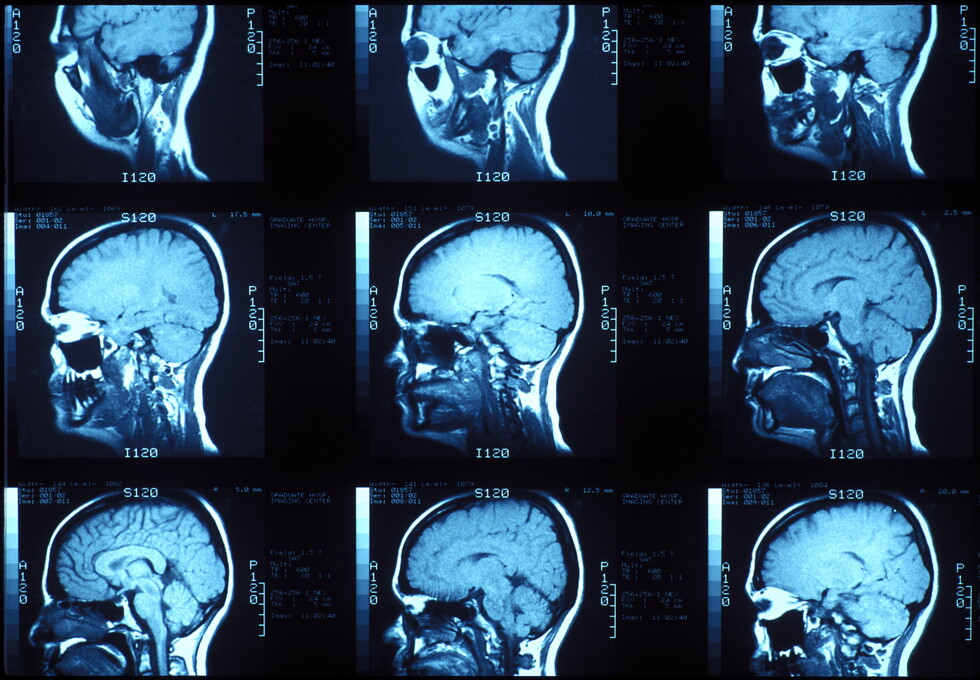

Σε κάθε περίπτωση, φαίνεται πως στους ανθρώπους το γεγονός της μείωσης του μεγέθους του εγκεφάλου δεν έχει επηρεάσει σημαντικά τόσο την ευφυΐα όσο και τις γνωστικές ικανότητες. Το 2018, μια ομάδα ερευνητών ανέλυσε έναν τεράστιο όγκο δεδομένων από τη UK Biobank, που περιέχει, μεταξύ άλλων, σαρώσεις εγκεφάλου και αποτελέσματα τεστ IQ για χιλιάδες ανθρώπους.

Η μελέτη διαπίστωσε ότι το να έχεις μεγαλύτερο εγκέφαλο συσχετίστηκε, κατά μέσο όρο, με μια ελαφρώς καλύτερη απόδοση στα τεστ IQ, αλλά αυτό δεν ήταν απαραίτητο. Αυτό σημαίνει ότι υπήρχαν μερικοί άνθρωποι που τα πήγαν πολύ καλά στα τεστ παρόλο που είχαν σχετικά μικρό εγκέφαλο και το αντίστροφο.